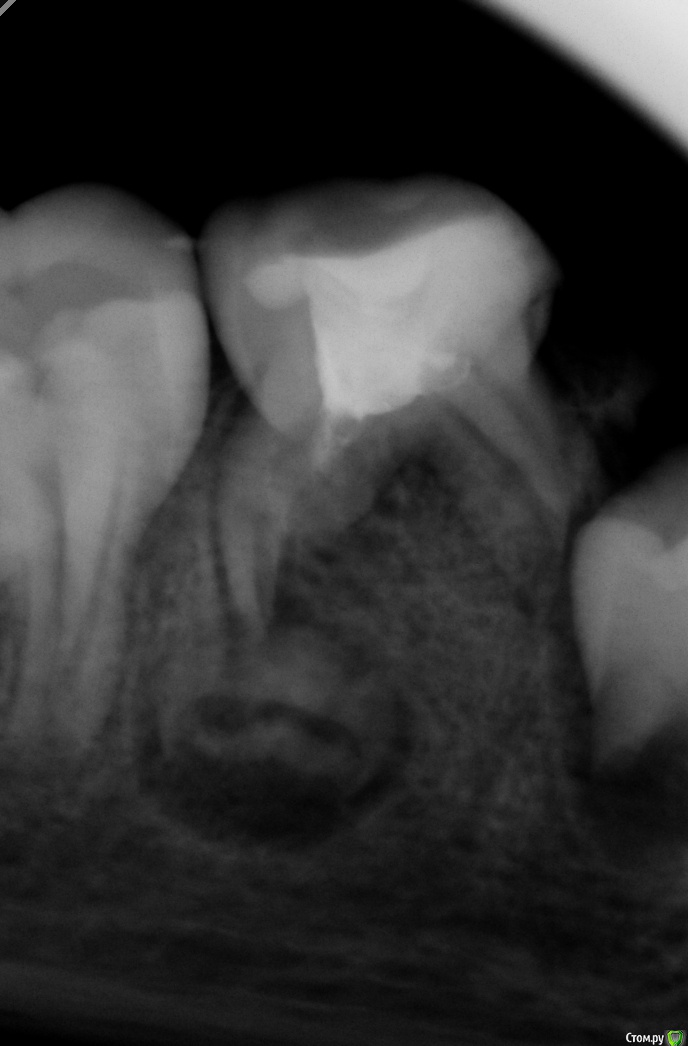

Усина Опубликовано 22 марта, 2018 Поделиться Опубликовано 22 марта, 2018 (изменено) Коллеги, подкажите как часто сталкивались с иволюцией зачатка постоянного зуба?тактика ведения таких больных?девочка 7,5 лет пришла с радиксом 8.4 зуба, на диагностическом снимке обнаружено инволюция зачатка постоянного зуба(8.5-лечен рф- методом)надо ли удалять 8.5? Изменено 22 марта, 2018 пользователем Усина Ссылка на комментарий

Усина Опубликовано 3 апреля, 2018 Автор Поделиться Опубликовано 3 апреля, 2018 Спасибо за совет!!!сравните развитие 4.4 и 4.5- мне кажется, мало вероятно, что 4.5 сформируется!на курсах А.Гецман рассказвала о инволюции зачатка постоянного зуба, думаю здесь именно это и происходит Ссылка на комментарий